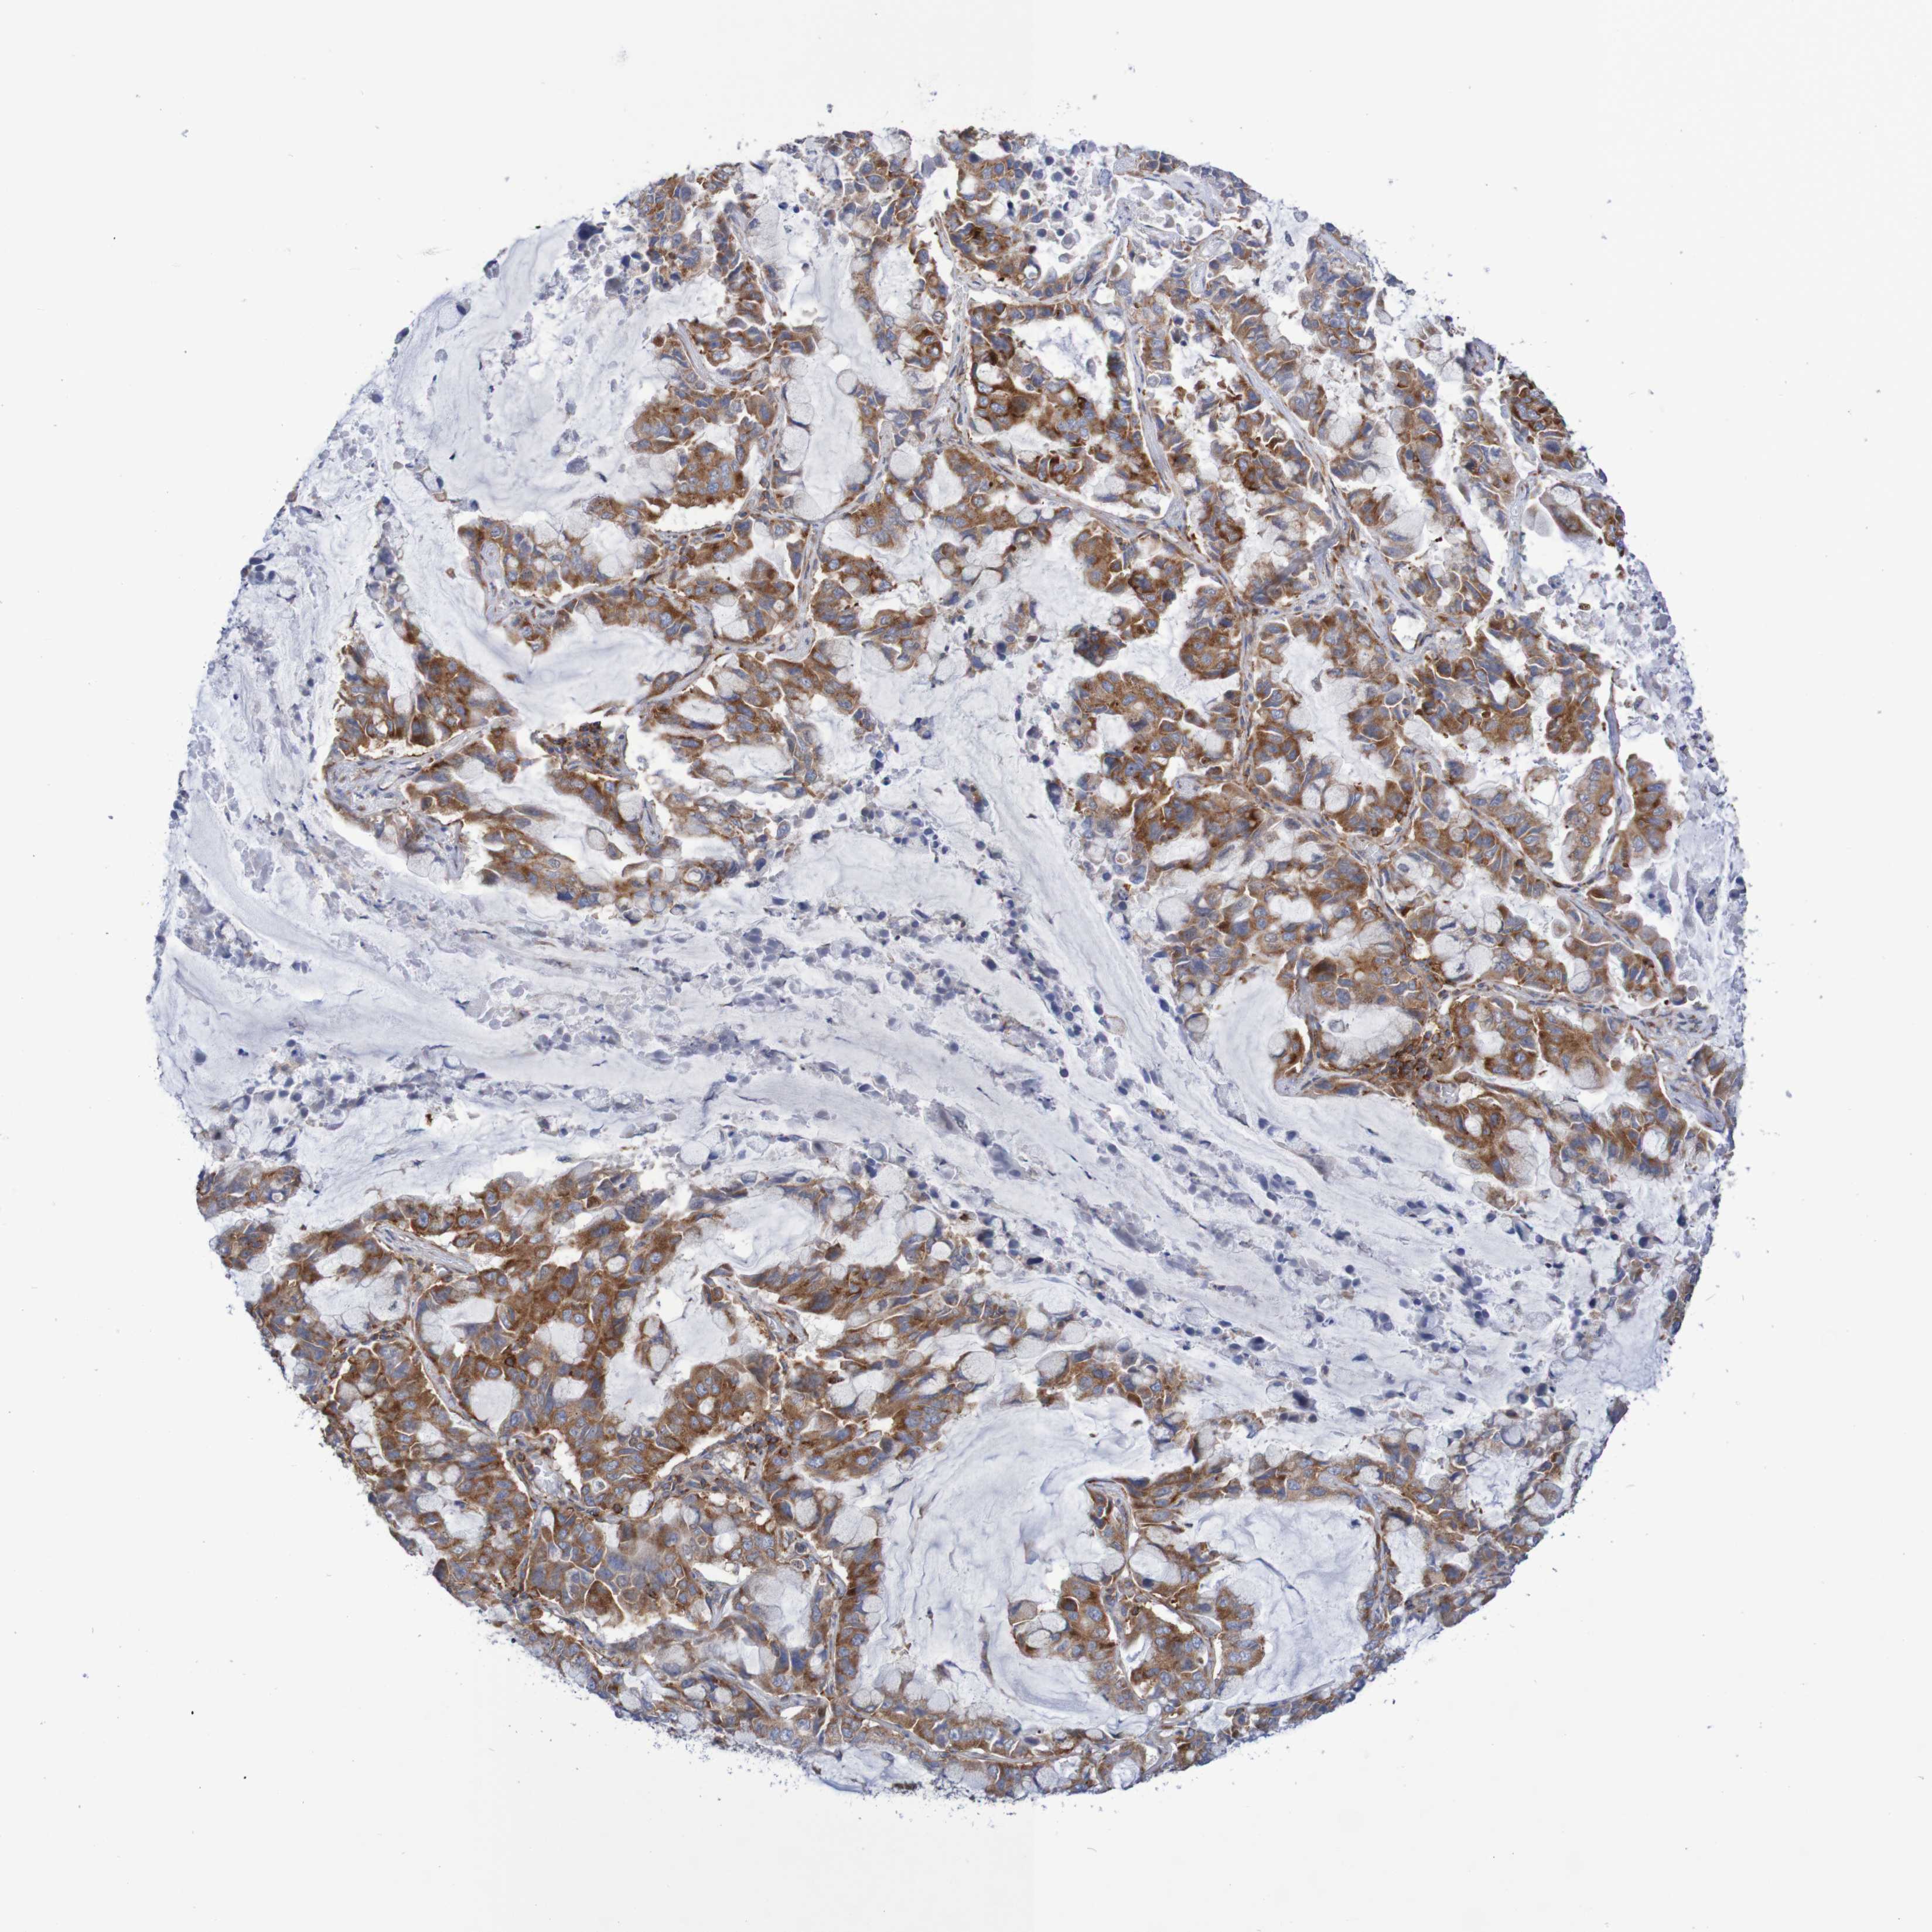

CANCER LUNG CANCER Show tissue menu

LUAD TCGA LUAD VALIDATION LUSC TCGA LUSC VALIDATION PROTEIN LUAD CPTAC PROTEIN LUSC CPTAC PROTEIN EXPRESSION

ANTIBODIES

AND

VALIDATION